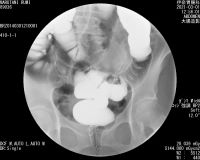

*直腸全摘手術前のレントゲン写真 (伊奈胃腸病院)

2021 3.22 直腸手術